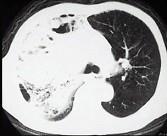

问题 男,30岁,咳嗽咯血,盗汗1个月,伴消瘦无力发热,CT如图,应考虑为 ( )

选项 A.右上肺大叶性肺炎 B.右上肺干酪性肺炎 C.右侧脓胸 D.右上肺多发肺脓肿 E.右上肺不张

答案 B